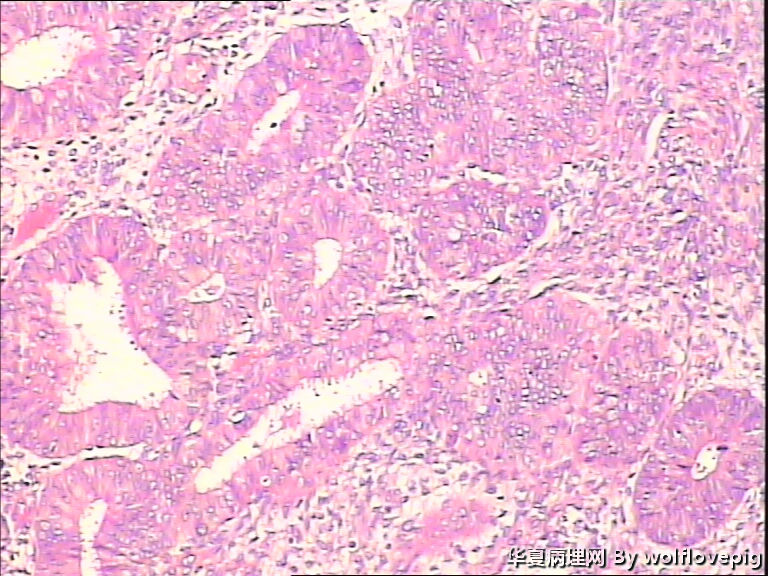

求助,子宫内膜!

48y

• 求助,子宫内膜!图3

图3